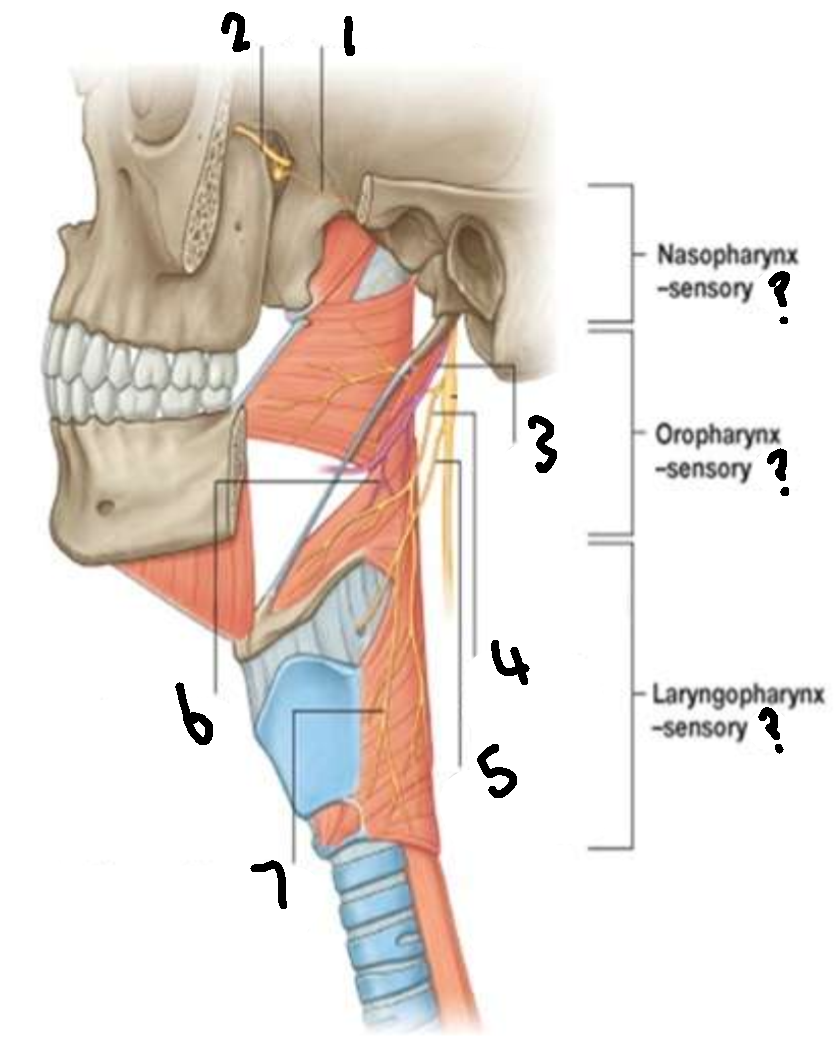

What provides sensory innervation to the nasopharynx?

mandibular branch of trigeminal V2

What provides sensory innervation to the oropharynx?

glossopharyngeal IX

What provides sensory innervation to the laryngopharynx?

vagus X

What is 1?

pharyngeal branch of V2

What is 2?

maxillary branch of trigeminal V2

What is 3?

glossopharyngeal IX

What is 4?

pharyngeal branch of vagus X

What is 5?

superior laryngeal nerve

What is 6?

pharyngeal branch of IX

What is 7?

external laryngeal branch of superior laryngeal nerve of X